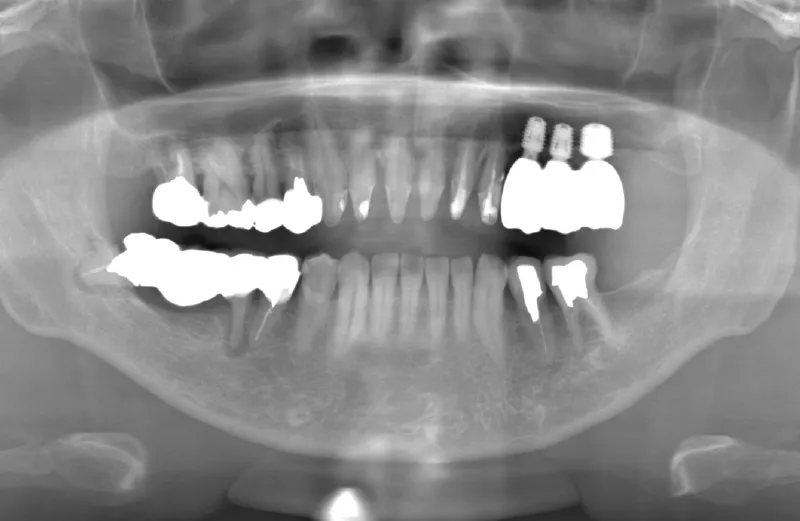

メガジェンオペの症例紹介02

治療前

治療後

| 主訴 | 左上の一番奥歯は他院にてマイクロスコープで治療してもらったが、根の状態が万全ではないのでブリッジでは治療しない方が良いと言われた。 なので左上の歯がないところにインプラントをして欲しい。 |

| 治療期間 | 2ヶ月で仮歯が入り、 3ヶ月で最終補綴物が入って終了。 |

| 費用 | 約550,000円 |

| 治療内容 | エクストラワイドショートインプラントを埋入し、上顎洞を移植材を用いずに挙上しインプラントを埋入した。約2ヶ月で仮歯を装着し、様々な機能面に問題がないことを確認し3ヶ月で最終補綴物を装着して終了した。 |

| 治療のリスク | インプラント埋入オペ時に術者が上顎洞内にインプラントを迷入させる可能性がある。これは術者が技術的に熟練していれば防ぐことが可能。 |